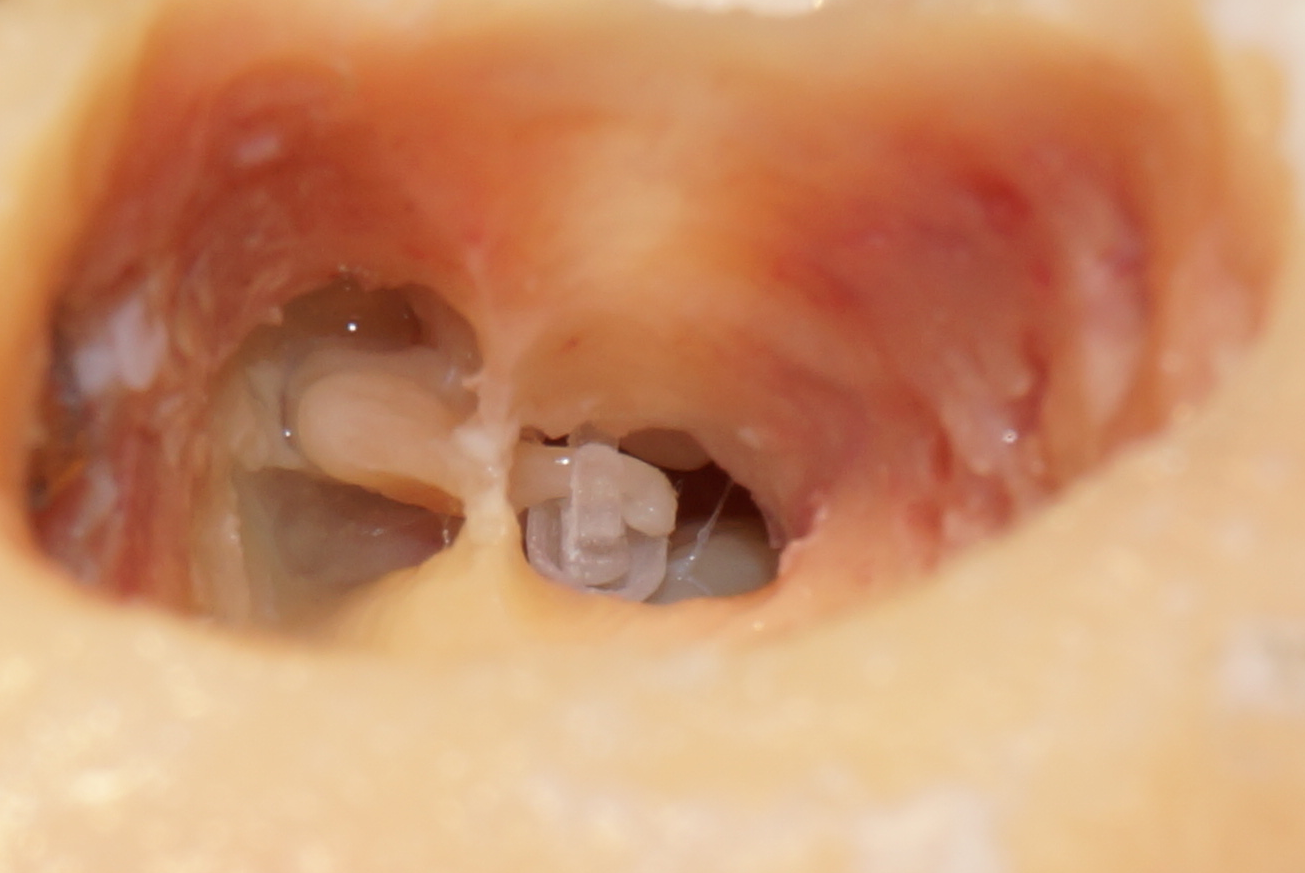

Prototype of a ventricular stapes prosthesis implanted in the middle ear (post mortem temporal bone preparation)

Prototype of a chamber stapes prosthesis implanted in middle ear (post mortem preparation of temporal bone).